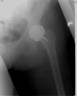

Xrays showed early osteoarthritis of the hip joint